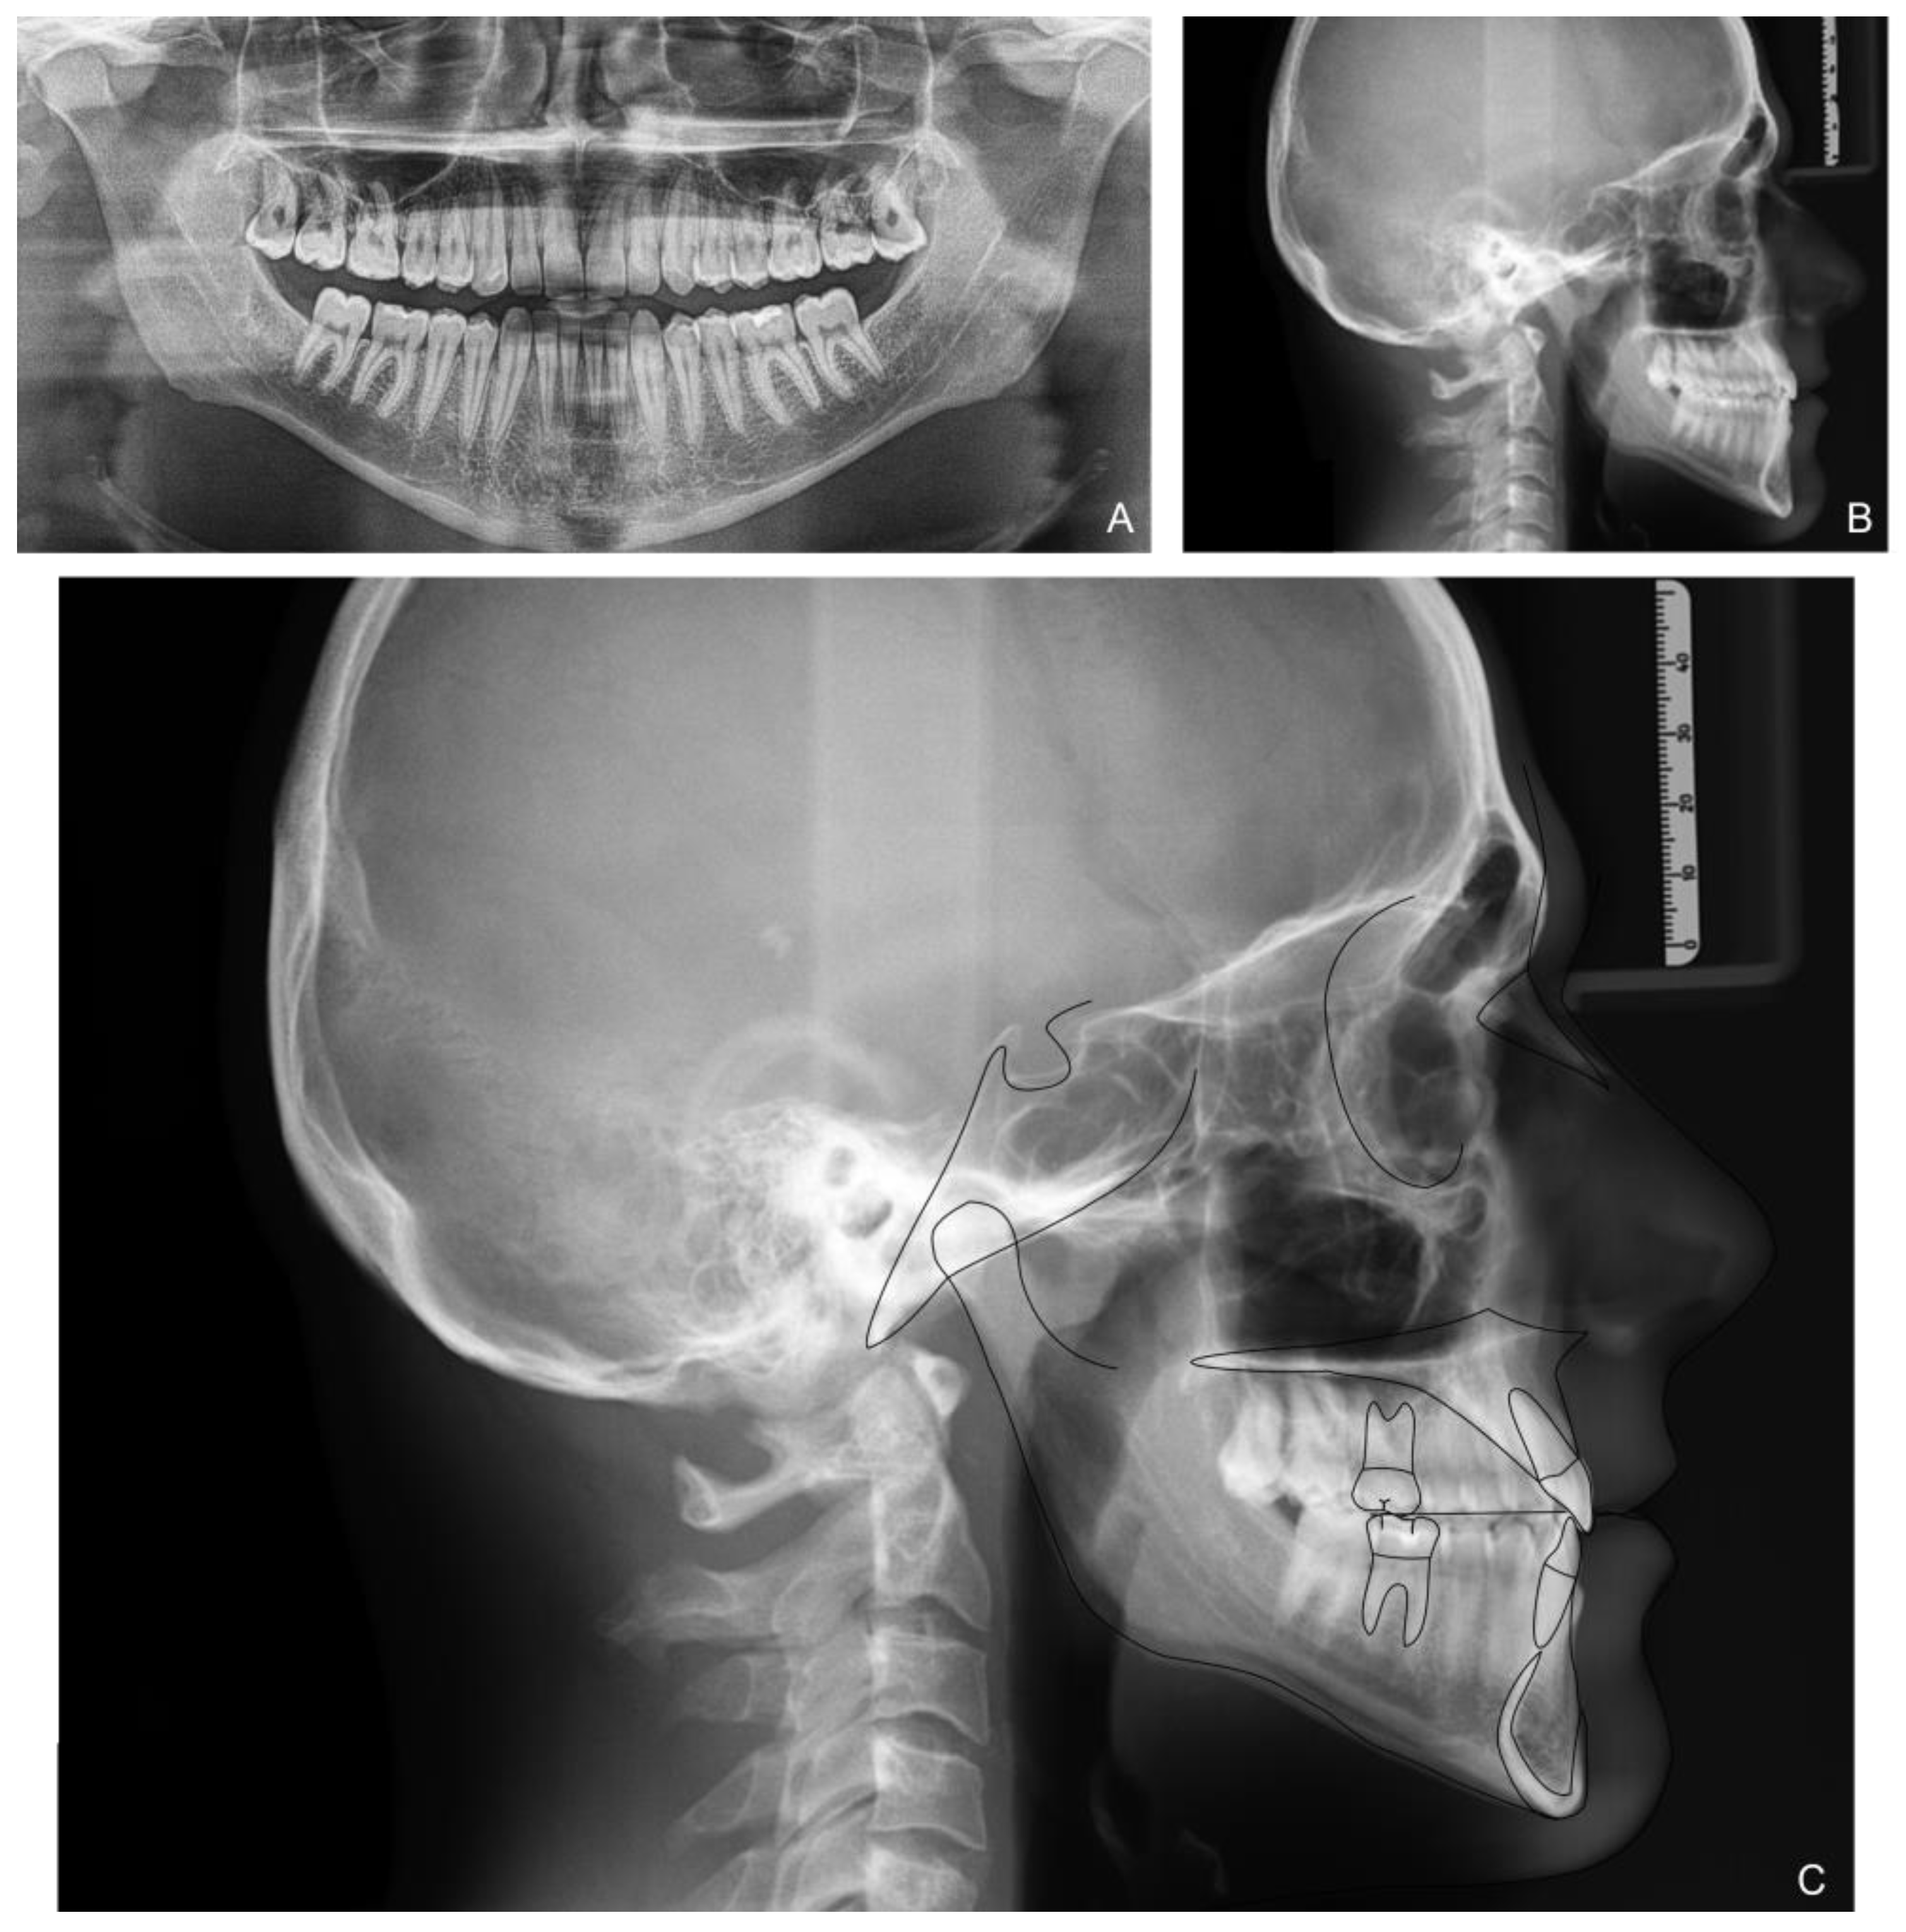

The orthopanoramic X-ray showed the physiological presence of all teeth and their good condition. The latero-lateral skull X-ray revealed a class III hyperdivergent skeletal malocclusion, a slight overbite and a negative overjet. Clinical examination also indicated minor teeth crowding with Angle class III malocclusion and head-to-head incisors relationship (Figure 2 and Table 1).

Figure 2. Patient X-rays, cephalometry tracing and analysis before treatment: panoramic X-ray (A); latero-lateral X-ray of the skull before treatment (B); Cephalometric tracing (C).

Table 1. Cephalometric values before treatment.